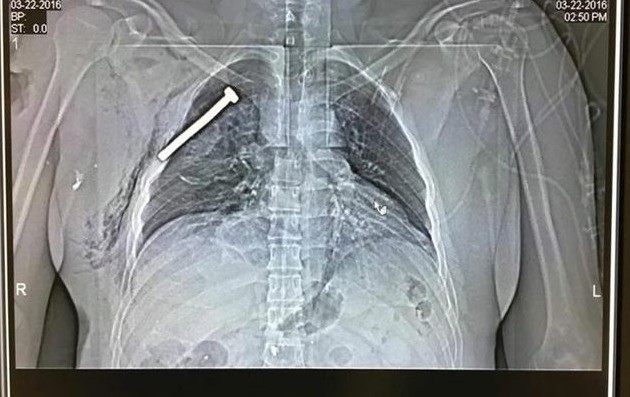

Η βόμβα που πυροδοτήθηκε από τους τζιχαντιστές στο αεροδρόμιο των Βρυξελλών και σκόρπισε το θάνατο, ήταν γεμάτη καρφιά για να έχουν σίγουρο και φρικτό θάνατο τα θύματα, σύμφωνα με το βελγικό δίκτυο VRT.

To ειδησεογραφικό δίκτυο επικαλείται γιατρούς του Πανεπιστημιακού Νοσοκομείου Leuven. Στο νοσοκομείο Leuven νοσηλεύονται αυτή τη στιγμή 11 θύματα των επιθέσεων με σοβαρούς τραυματισμούς, ενώ η κατάσταση των τριών από αυτά χαρακτηρίζεται ως κρίσιμη.